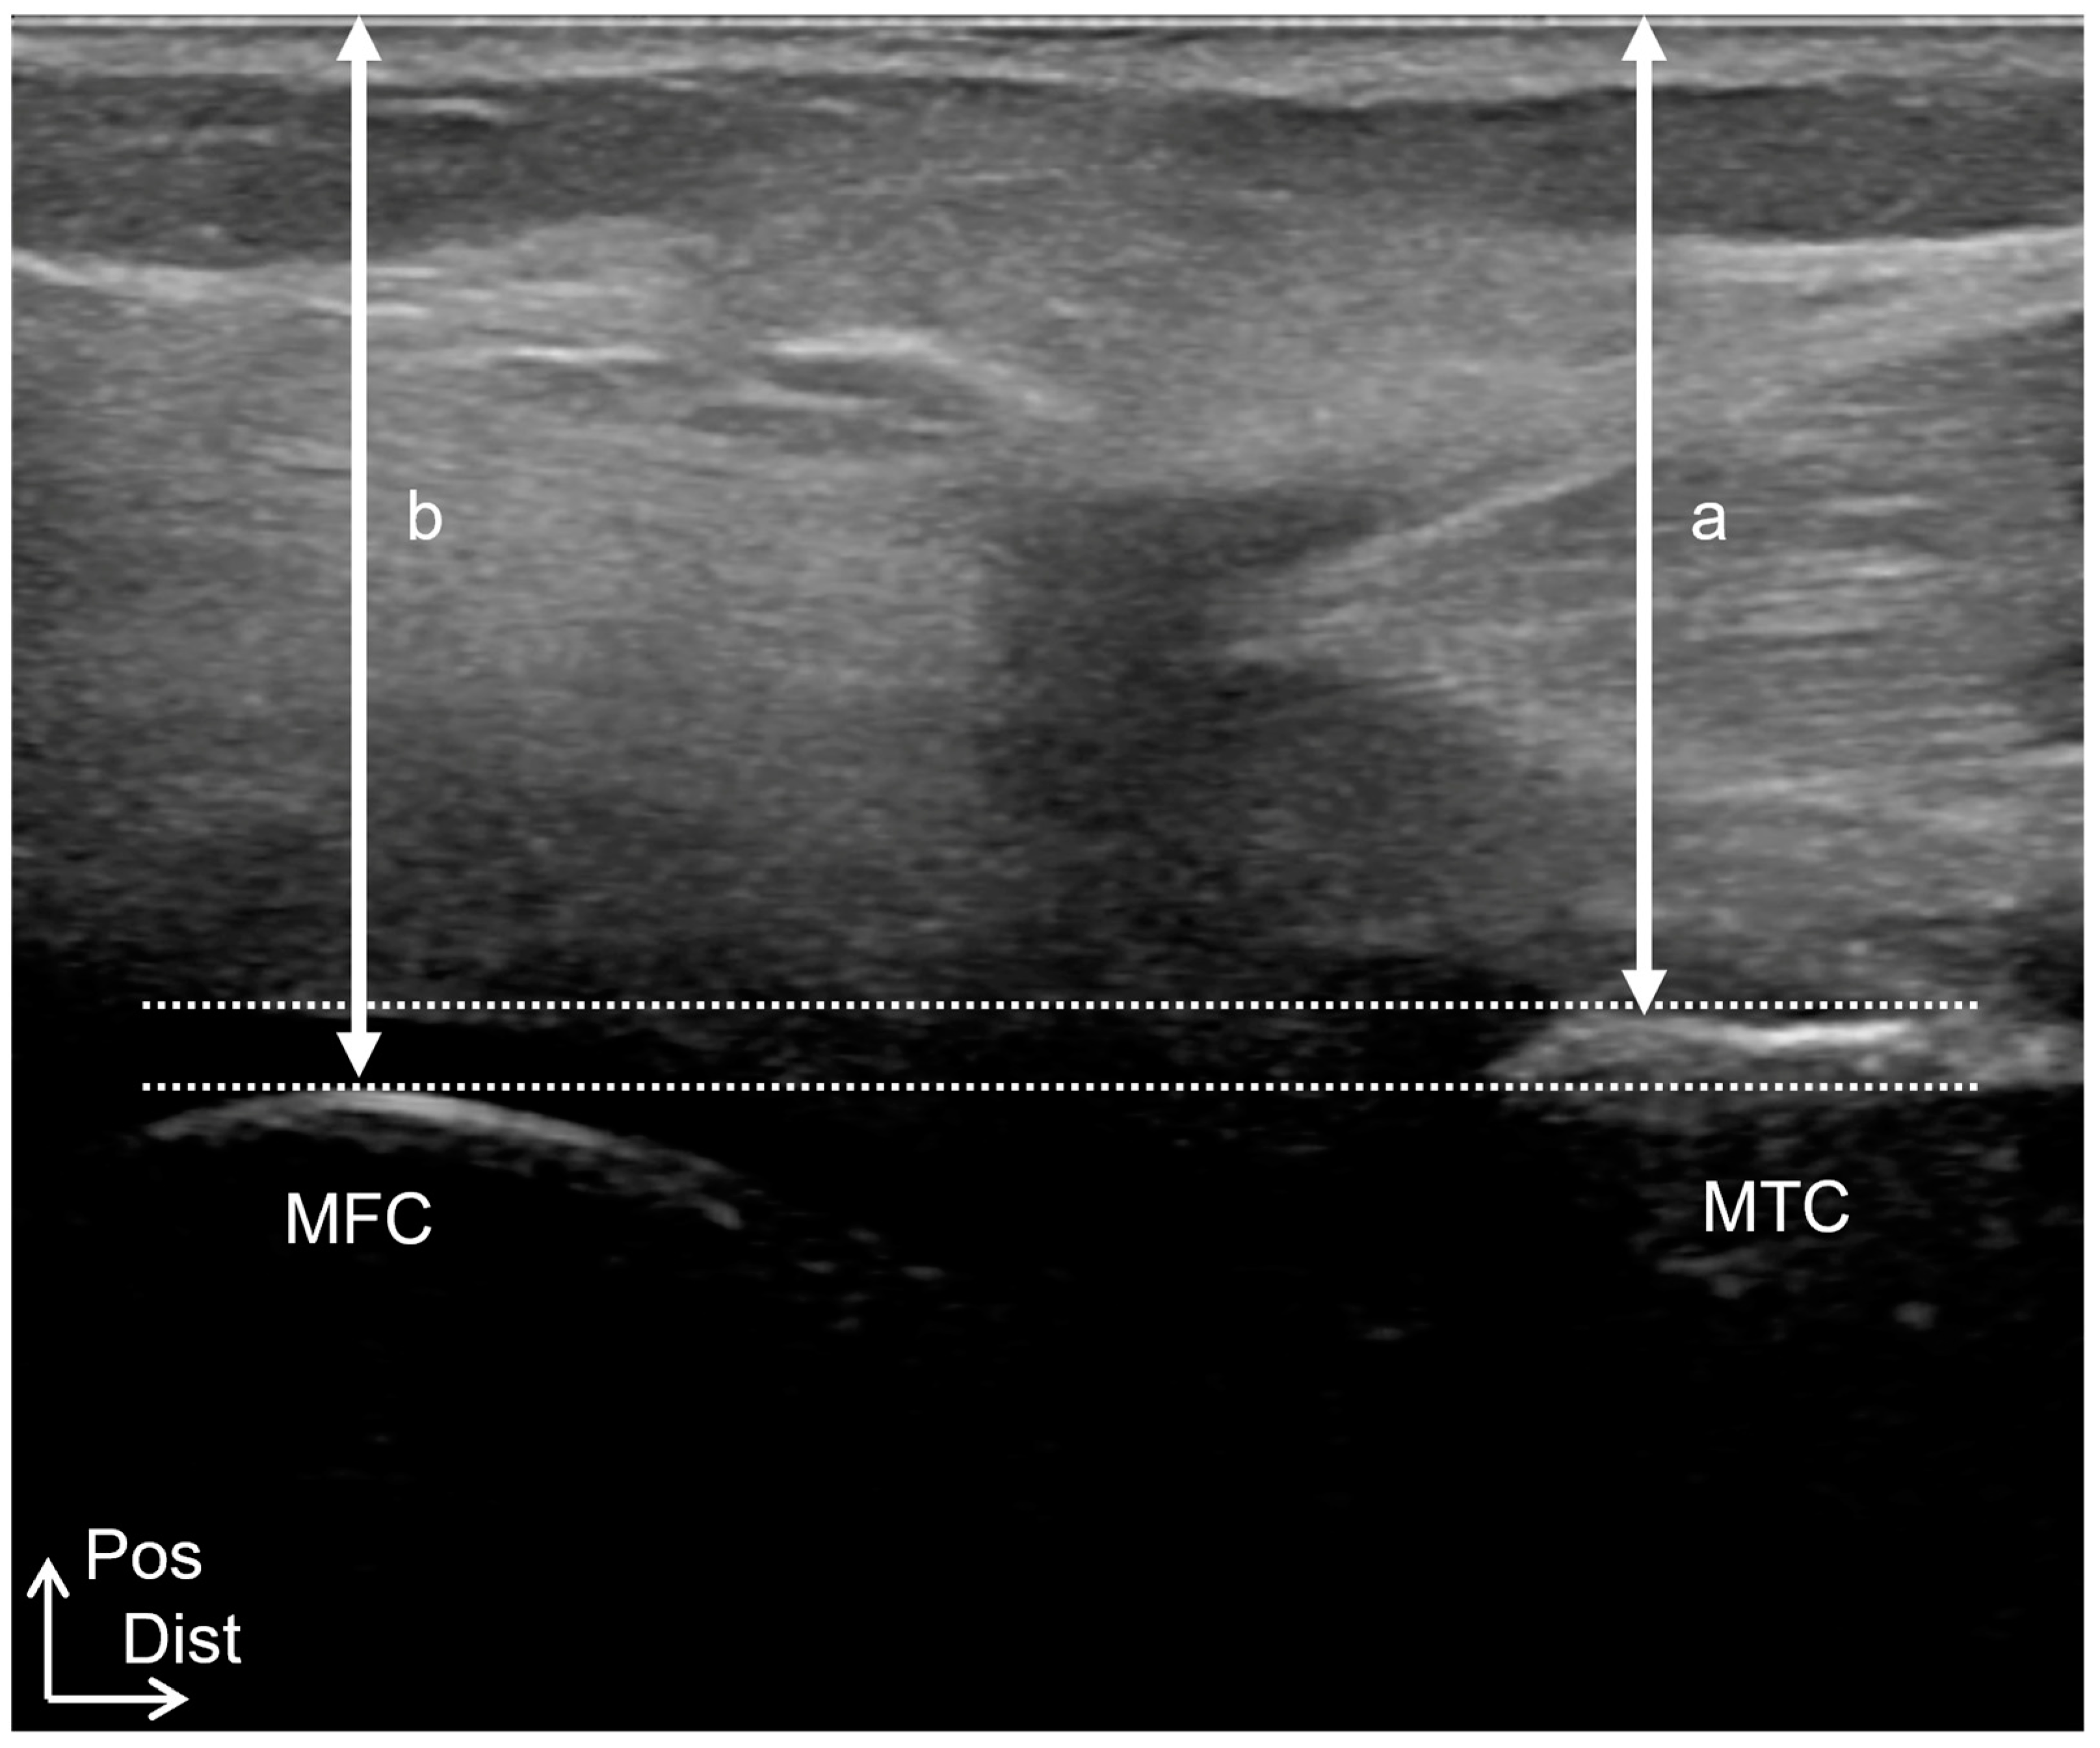

Ultrasound imaging examinations were performed using a SONIMAGE HS1 (KONICA MINOLTA, Tokyo, Japan) with an 18 MHz linear transducer in B-mode. Measurements were performed with the patients in the prone position on a bed, with the knee joint in full extension and the center of the patella positioned at the edge of the bed. A physical therapist performed the ultrasound imaging measurements. The probe was placed at the popliteal fossa, and the most prominent posterior points of the medial femoral and tibial condyles and the most prominent posterior points of the lateral femoral and tibial condyles were visualized on the long-axis images (Figure 1). The medial condyle gap was calculated as the difference between the distance from the most prominent posterior medial tibial condyle to the skin and the distance from the most prominent posterior medial femoral condyle to the skin. The lateral condyle gap was calculated as the difference between the distance from the most prominent posterior lateral tibial condyle to the skin and that from the most prominent posterior lateral femoral condyle to the skin. The mediolateral (ML) gap was calculated by subtracting the lateral condyle gap from the medial condyle gap. The ML gap was assigned a positive value for external rotation and a negative value for internal rotation.

Figure 1.

Ultrasound imaging measurement method. (A) Probe irradiation sites of medial femoral and tibial condyles. (B) Long-axis image of the most prominent posterior point of the medial femoral condyle and the most prominent posterior point of the medial tibial condyle. (C) Probe irradiation sites of lateral femoral and tibial condyles. (D) Long-axis image of the most prominent posterior point of the lateral femoral condyle and the most prominent posterior point of the lateral tibial condyle. a, the distance from the most prominent posterior medial tibial condyle to the skin. b, the distance from the most prominent posterior medial femoral condyle to the skin. c, the distance from the most prominent posterior lateral tibial condyle to the skin. d, the distance from the most prominent posterior lateral femoral condyle to the skin. MFC, medial femoral condyle; MTC, medial tibial condyle; LFC, lateral femoral condyle; LTC, lateral tibial condyle; Sup, superior; Lat, lateral; Pos, posterior; Dist, distal.

Tibiofemoral joint alignment was based on ultrasound imaging examinations in Study 1. The distance between the posterior margins of the femoral and tibial medial condyles was deemed the medial condyle gap, and the distance between the posterior margins of the femoral and tibial lateral condyles was measured as the lateral condyle gap (Figure 1). The ML gap was calculated by subtracting the lateral condyle gap from the medial condyle gap.